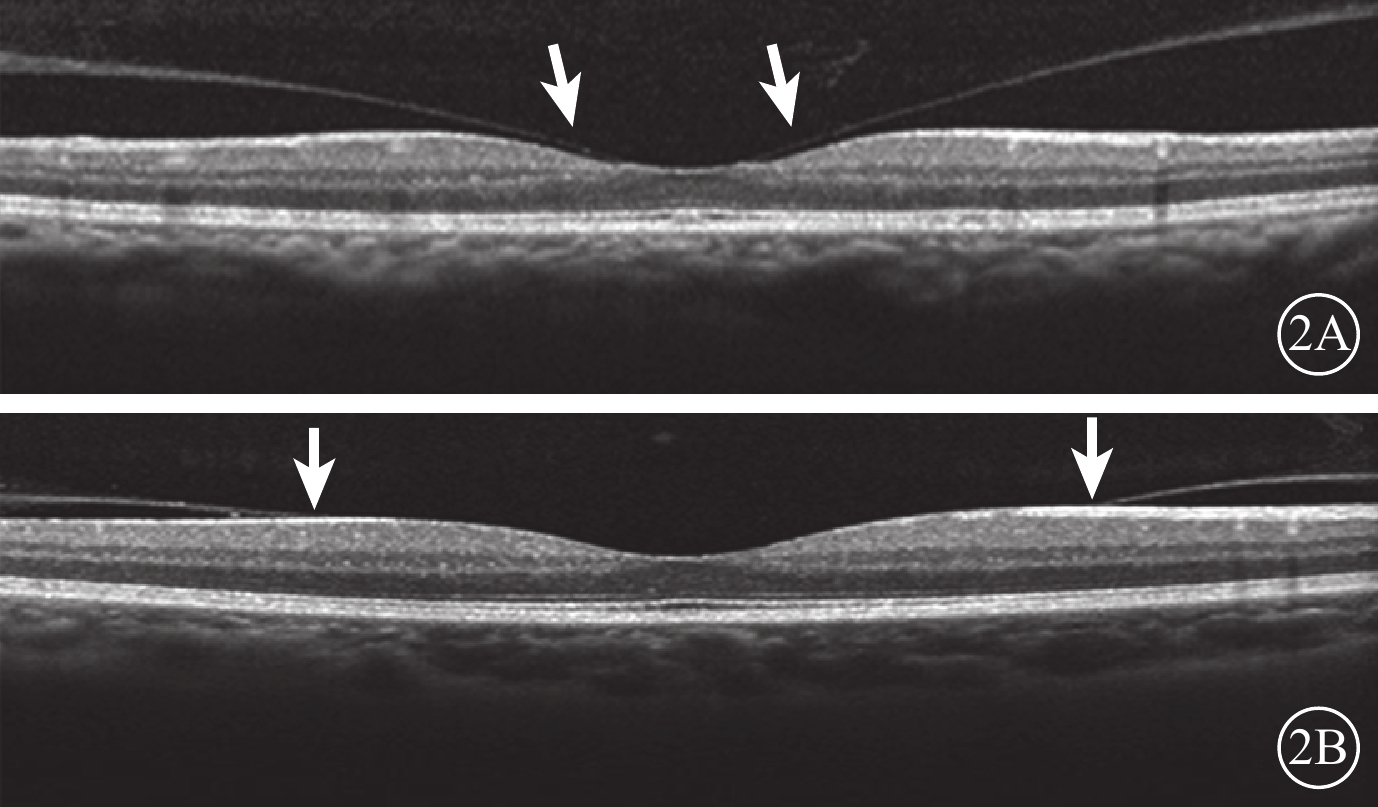

末次隨訪時,34只研究眼中,VMI異常12只眼。其中,廣泛型VMA 5只眼,局灶型VMA 2只眼,C-PVD 3只眼,MEM 2只眼;合并存在C-PVD、MEM 1只眼。與治療前比較,共有6只眼VMI發生變化(圖3)。34只對照眼中,VMI異常13只眼。其中,廣泛型VMA 5只眼,C-PVD 7只眼,MEM 1只眼。與治療前比較,共有6只眼VMI發生變化(圖4)。治療前研究眼中局灶型VMA 3只眼,其末次隨訪時發生C-PVD 2只眼。治療前對照眼中局灶型VMA 2只眼,末次隨訪時均發生C-PVD(表1)。